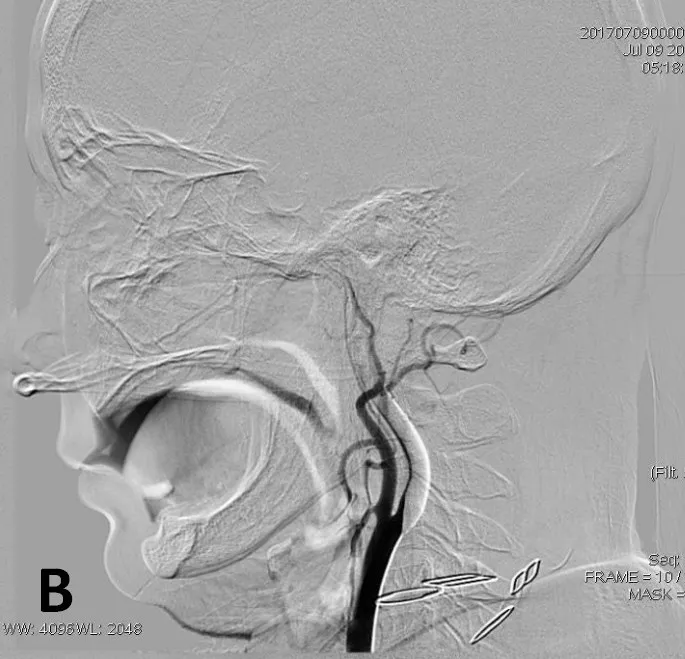

侧支循环评估提示右侧大脑后动脉、大脑前动脉(ACA)皮层支发挥部分代偿作用。

大脑后动脉

大脑前动脉